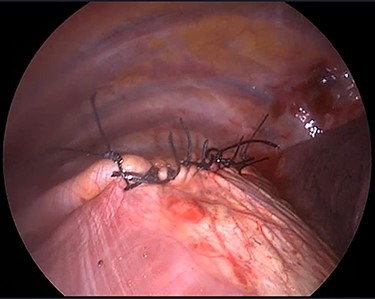

The operation was performed under general anaesthesia with the patient intubated using a double-lumen endotracheal tube. A 4 cm incision was made in the right sixth intercostal space in order to locate the mass. After the insertion of a 10 mm 30-degree thoracoscope, a rounded smooth-surfaced, broad necked mass attached to the right hemidiaphragm was visualized (Fig. 3). The decision to open the diaphragm was made. Further dissection and exploration with an energy device revealed that the mass which was bounded superiorly in the form of a pouch by the diaphragm and had arisen from the liver (Fig. 4). The mass was completely resected with HARMONIC ACE® +7 (Ethicon) after consulting with the hepatobiliary surgeon who felt there was a clear cleavage plane between the mass and liver. The exposed area of liver was covered with Floseal®(Baxter) and TachoSil®(Takeda). The diaphragmatic defect (Fig. 5) was closed in a single layer with 10 simple interrupted silk sutures (Fig. 6). The remainder of the surgery was uncomplicated, and the patient was discharged home on the second postoperative day. Subsequent histology findings reported the mass as benign (accessory) hepatic tissue (Fig. 7).

Diaphragmatic defect was closed in a single layer with simple interrupted stitches.